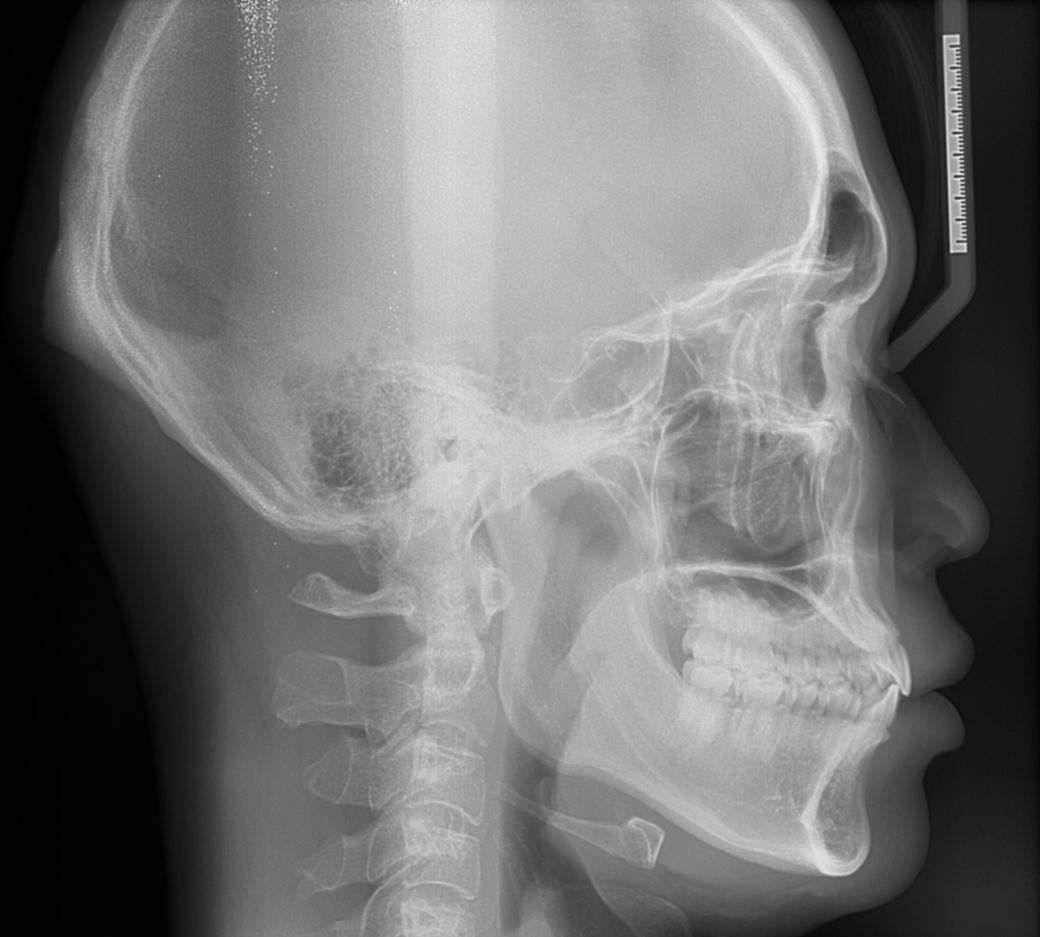

미세돌출입 때문에 3군데에서 교정상담을 받았는데 치아교합이 전체적으로 좋고 치아각도도 좋다고 했습니다 대신 앞니치근이 짧고 약간의 하악비대칭이있다고 했습니다.

A치과는 평균남성보다 하관이 크고 조금 턱이 나와서 입이 전체적으로 나와보이는 거라서 구강악안면외과가서 양악이나 윤곽수술상담을 받아보라고 했습니다.

세가지 치과 모두 맞는 말입니다. 지금 보여주신 자료를 종합해보면 경미한 3급 부정교합입니다.

이 상태에서 교정도 가능하고 양악도 가능하지만 치료 이후 변화되는 모습에는 한계가 있습니다. 또한 부정교합 및 골격부조화가 심하지 않으므로 심미적으로 불편감이 없다면 3번 치과처럼 치료하지 않아도 됩니다. 물론 심미적으로 문제가 된다고 생각한다면 이때는 두가지 방법 모두 가능합니다.

다만 양악수술은 확실히 골격 부조화를 잡아줄 수 있다면 교정에는 한계가 있으니 전문가와 상담이 필요합니다.